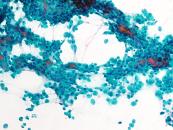

第40回日本臨床細胞学会九州連合会学会(大分)スライドカンファレンス症例1

種別:婦人科

出題:橋口 真理子 佐賀大学医学部病因病態科学講座

| 年齢 | 10代 | 性別 | 女性 |

| 採取部位 | 右卵巣腫瘍 | 採取方法 | 捺印細胞診 |

既往歴 特になし

妊娠出産歴 未経妊未経産

現病歴 手術の2か月前頃から腹部膨満感を自覚し近医受診。腹部エコーで骨盤内に17㎝大の充実性腫瘤を指摘され当院受診。右側卵巣腫瘍の診断で手術が施行された。右付属器切除術が行われ、術中迅速に提出された。右卵巣は20㎝程度に腫大し、割面は黄白色調で充実性腫瘤であった。捺印細胞診を採取した。

術前の採血では、hCG329mIU/ml (1.0 以下)、AFP3.3ng/ml(0~7.0)、CA125 92 U/ml (0-35)、LDH 2772U/L (124-222)であった。

| 正解 | 2.Dysgerminoma |

▼選択肢及び投票結果

| 1.Yolk sac tumor | 17件 | (16.2%) | |

| 2.Dysgerminoma | 77件 | (73.3%) | |

| 3.Granulosa cell tumor | 2件 | (1.9%) | |

| 4.Clear cell carcinoma | 7件 | (6.7%) | |

| 5.Neuroendocrine carcinoma | 2件 | (1.9%) | |

| 投票総数 | 105件 | (100%) |